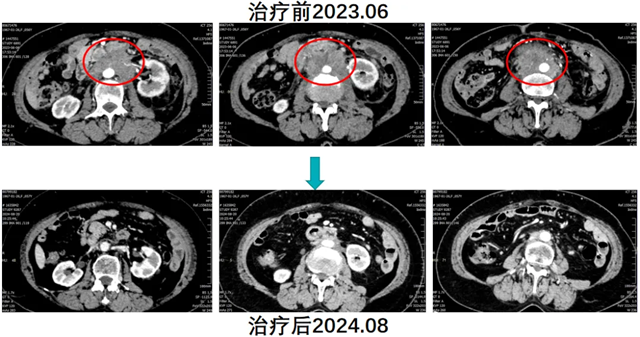

林女士因“腹痛”就诊内江市第二人民医院肿瘤四科(头颈盆腔食管肿瘤科),完善检查后诊断为子宫内膜样腺癌术后腹腔及盆腔多发淋巴结转移。结合患者临床表现、病史及影像学检查,考虑患者肿瘤进展、瘤负荷大、贫血重,且对传统免疫联合化疗无效,腹痛症状给生活质量带来严重影响。

经肿瘤四科(头颈盆腔食管肿瘤科)团队充分讨论,建议患者行腹主动脉旁淋巴结空间分割放疗联合免疫治疗(卡瑞利珠单抗)及生物治疗(人粒细胞巨噬细胞刺激因子)。与患者及家属沟通病情并经同意后,实施了上述治疗方案。放疗后患者返院高兴的讲述道腹部疼痛已经没有了,复查CT显示腹腔淋巴结明显缩小,治疗效果显著,续继免疫维持治疗。患者肿瘤持续缩小、生活质量明显提高,今年8月复查显示肿瘤基本消失。

患者就诊时已属于晚期子宫内膜癌,且对免疫联合化疗耐药,可选择治疗手段非常有限。患者如果不尝试“鸡尾酒”(空间分割放疗联合免疫及生物治疗)式疗法,预计生存时间不超过半年。通过“鸡尾酒”疗法成功逆转了免疫耐药,极大地延长了患者的生存时间,明显提升了患者的生存质量。